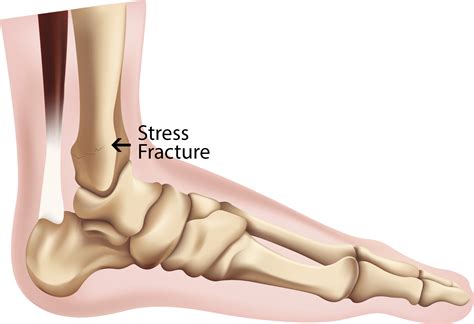

Understanding Stress Fractures

A stress fracture is a small crack in a bone caused by repetitive force, often from overuse. Unlike acute fractures resulting from a single traumatic event, stress fractures develop gradually. The heel bone, or calcaneus, is particularly susceptible to stress fractures due to the significant weight and pressure it bears during daily activities.